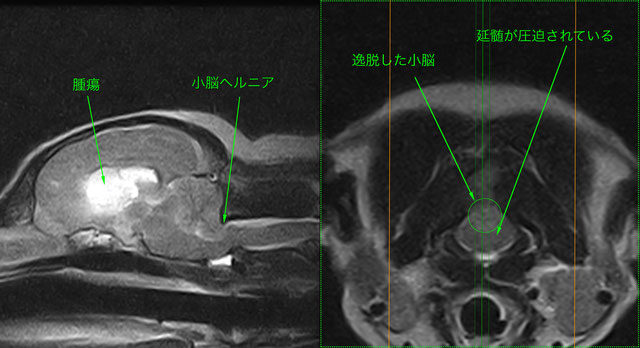

脳ヘルニア(Brain Herniation)

小脳ヘルニア(大孔ヘルニア)

上記と同一症例

意識レベルが徐々に低下し、一時的に心肺停止となる。蘇生処置を行い、直ちにMRI撮影

脳腫瘍が原因の脳圧亢進により、小脳が頭蓋骨外へ逸脱し延髄を圧迫

脳波検査などで大脳死を確認、安楽死